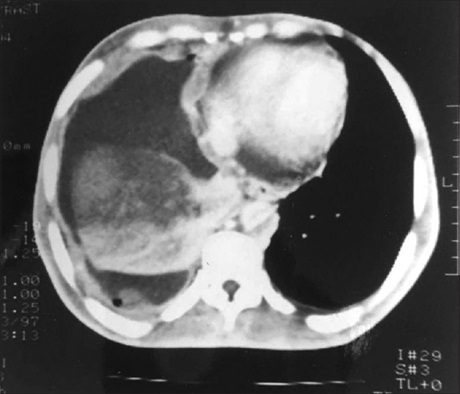

Malignant Infantile Osteopetrosis

L Appaji, BS Aruna Kumari, K Govind Babu, Dr. Gita R Bhat (Author)

76-78